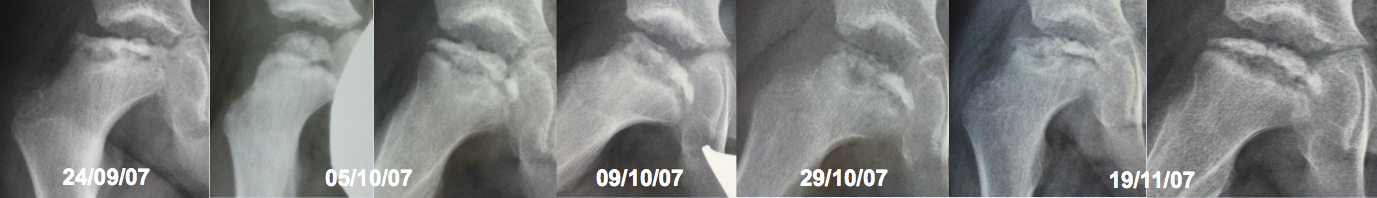

Enfermedad de Legg-Perthes-Calvé recurrente. Descripción de un caso y revisión de la literatura. [Recurrent Legg-Perthes-Calvé disease. A case report and literature review]